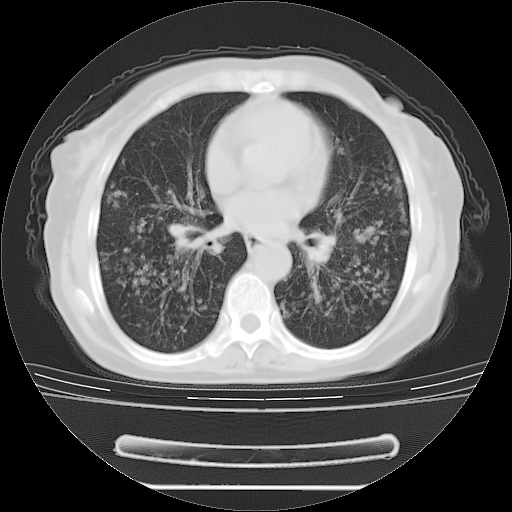

患者女性,72岁,慢性咳嗽3月余,曾抗炎治疗无效果,最近抗结核治疗约半月余,症状缓解。

ct示两肺粟粒状病灶,以两肺上叶尖后段及下叶背段分布为主;首先考虑结核。请战友们分析。

考虑 1 弥漫性泛细支气管炎, 2 结核不除外/.  有小叶中心结节 和 树芽征!!

两肺内病灶呈小结节状和树芽状,纵膈的肿大的淋巴结密度不均匀,并见有钙化,考虑为两肺结核可能更大些。

两肺内病灶呈小结节状和树芽状,纵膈的肿大的淋巴结密度不均匀,并见有钙化,多形态病灶,考虑为两肺结核,肝内考虑小囊肿。

增殖性多发性病灶,大小不一,分布不均匀,发生于肺泡中,纵隔淋巴结肿大其内有钙化,诊断:细支气管肺泡癌,

病灶以结节为主,大部分边界清楚,分布不均,病灶形态较单一,偶见空泡征,纵膈淋巴结肿大钙化,无结核中毒症状考虑 感染性病变【真菌类可能性大】,细支气管肺泡癌。其他待排

片子很好,质量很高,两侧肺门淋巴结肿大并有钙化,两肺弥漫病灶,首先考虑tb并播散,但年龄大了呀(72岁)小细胞肺癌不能除外,如果是肺癌也没什么大的治疗了,建议正规抗结核治疗后复查

支持亚急型粟粒性结核